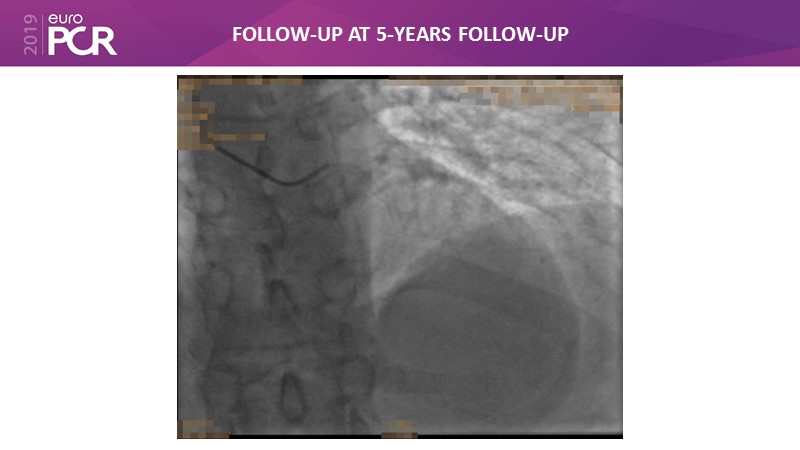

Consult this session to get insights about the need for a dedicated drug eluting stent (DES), as well as the benefits of a DES+DCB strategy, for diabetes mellitus (DM) and acute MI (AMI) patients.

- To understand and discuss the need for a dedicated DES for diabetes mellitus (DM) and acute MI (AMI) patients

- To understand and learn benefits of DES+DCB strategy to provide uniform and homogenous drug delivery in patients with diabetes mellitus and acute MI